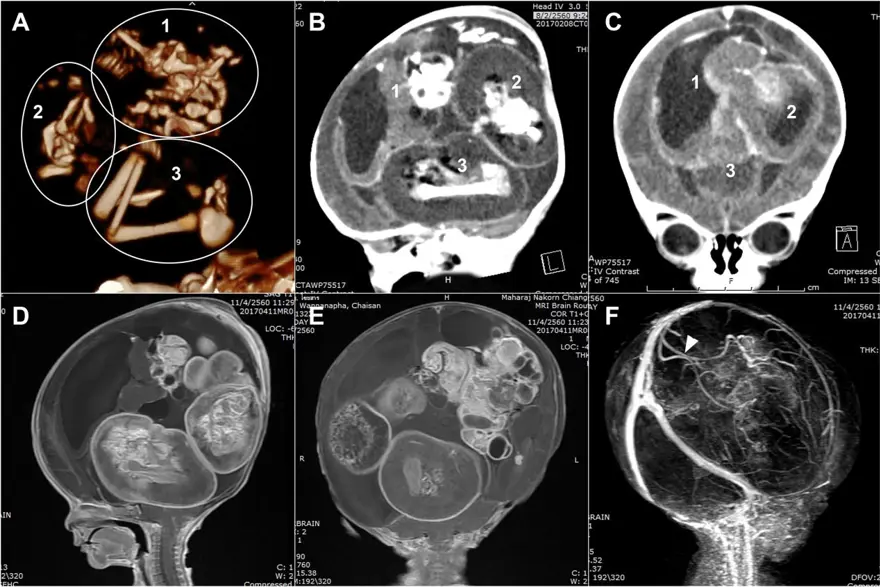

Çin'de doğmamış ikizinin fetüsü, bir yaşındaki kız bebeğin kafatasından ameliyatla çıkarıldı. 'Fetüs içinde fetüs' adı verilen oldukça nadir vakada, doktorlar fetüsün üst uzuvlarının, kemiklerinin ve hatta tırnaklarının gelişmiş olduğunu, yani kardeşinin içindeyken aylarca büyümeye devam ettiğini söyledi.Yaklaşık beş santim uzunluğundaki fetüs, ancak ebeveynler kızlarını kafası büyüdüğü ve motor becerilerinde sorunlar yaşadığı zaman doktora götürdüklerinde fark edildi.

Şangay'daki doktorlar, doğmamış ikizin fetüsünün çocuğun beyninde geliştiğini tespit etti. Çalışmanın yazarları, "Motor becerilerinde gecikmesi ve genişlemiş baş çevresi olan 1 yaşındaki bir kız çocuğunda malforme olmuş monokoryonik diamniyotik ikiz olan intraventriküler fetüs içinde fetüs (fetus-in-fetu) tespit edildi." denildi.

Parazit ikiz olarak da adlandırılan fetüs içinde fetüs, ikizlerin rahimde yapışık olması, ancak yalnızca birinin gelişmeye devam etmesi durumunda ortaya çıkıyor. Çalışmada, genom dizilimi sonrasında fetüsün çocuğun ikizi olduğunun tespit edildiği de belirtildi.

Bununla birlikte fetüs içinde fetüs vakaları ikiz gebeliğin çok erken aşamalarında, döllenmiş bir yumurta tarafından oluşturulan ve blastosist olarak adlandırılan bölünen hücre kümesinin düzgün bir şekilde ayrılamamasıyla meydana geliyor. Ardından embriyolardan biri diğeri tarafından çevreleniyor. Diğer ikizin çoğalan hücreleri tarafından sarılan öteki fetüs gelişemiyor, ancak kan desteği aldığı için "canlı" kalıyor.